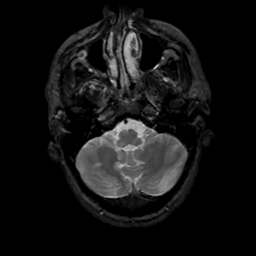

MR Study #13, May 19, 1991 -- Slice #9

[Home][Help][Clinical][Tour 1][Tour 2] Slice 9